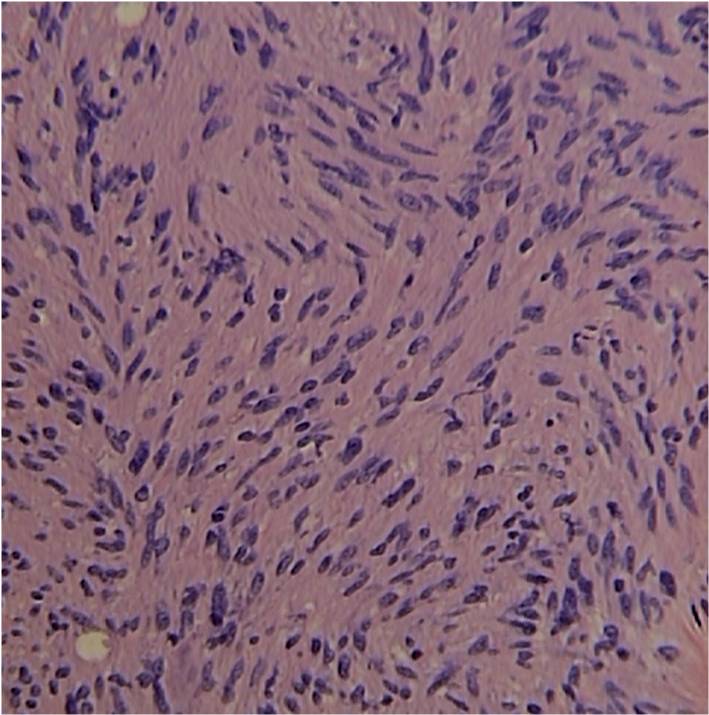

• Distinct Pattern of alternating Antoni A and B areas

o Antoni A Area: Cellular area arranged in short bundles or interlacing fascicles

Spindle cells with wavy appearing nuclei. (Fig. 5 & 6)

Fig. 5-7 Microscopic Pathology demonstrates 2 different patterns; Antoni A area with spindled hypercellular distribution with wavy appearing nuclei (Fig 5 & 6A) that palisades, known as Verocay Bodies (Fig 6B). Antoni B area is less cellular and more myxoid (Fig 7) than the Antoni A area. Mitotic activity is not visible.